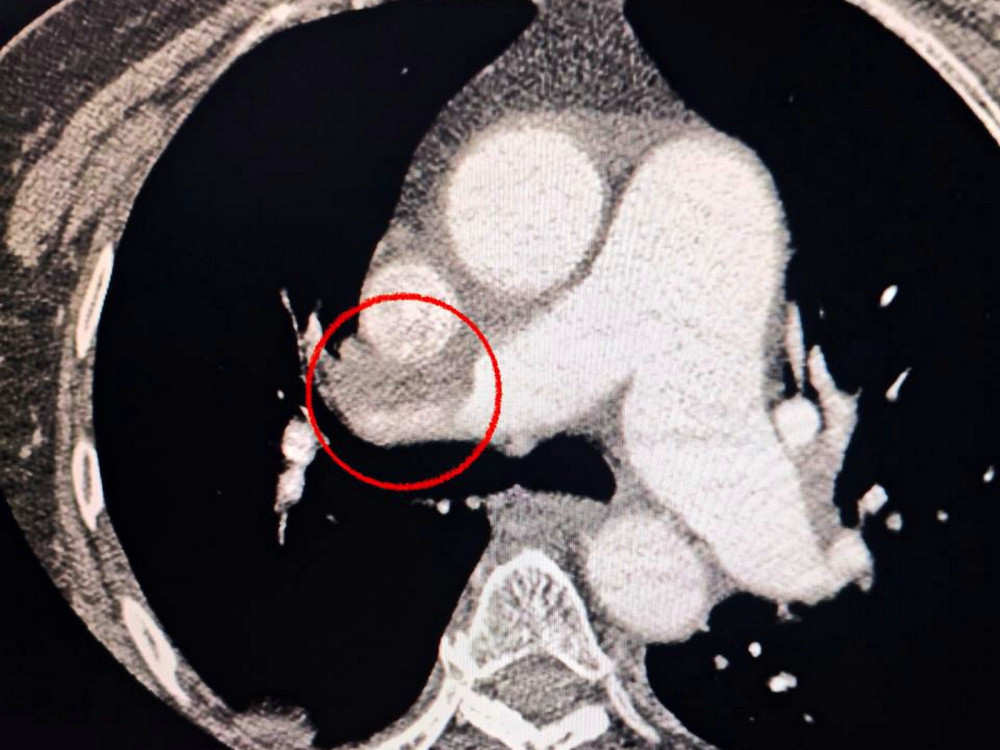

Жінка була доставлена до лікарні з серйозним нападом інсульту. Під час комп'ютерної томографії медики виявили блокаду середньої мозкової артерії.

Крім того, лікарі звернули увагу на те, що пацієнтці складно дихати, тому вона пройшла додаткове обстеження легень, яке виявило тромбоемболію.